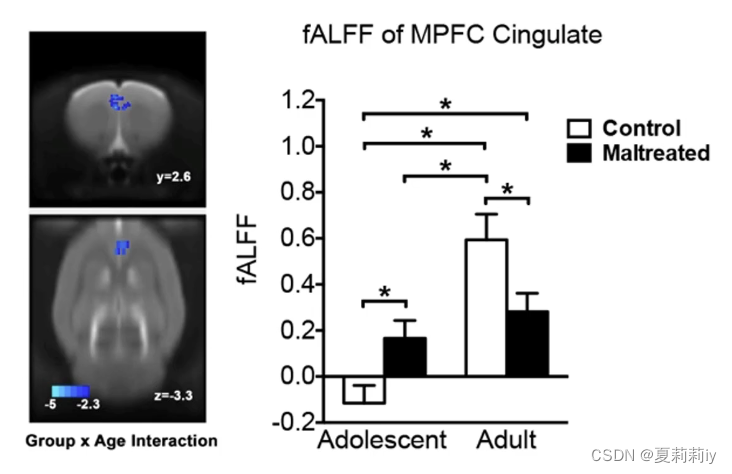

(8)Mixed Effect Analysis

①做混合设计,既有被试内因素,也有被试间因素

②得到的文件,最重要的是中间那个